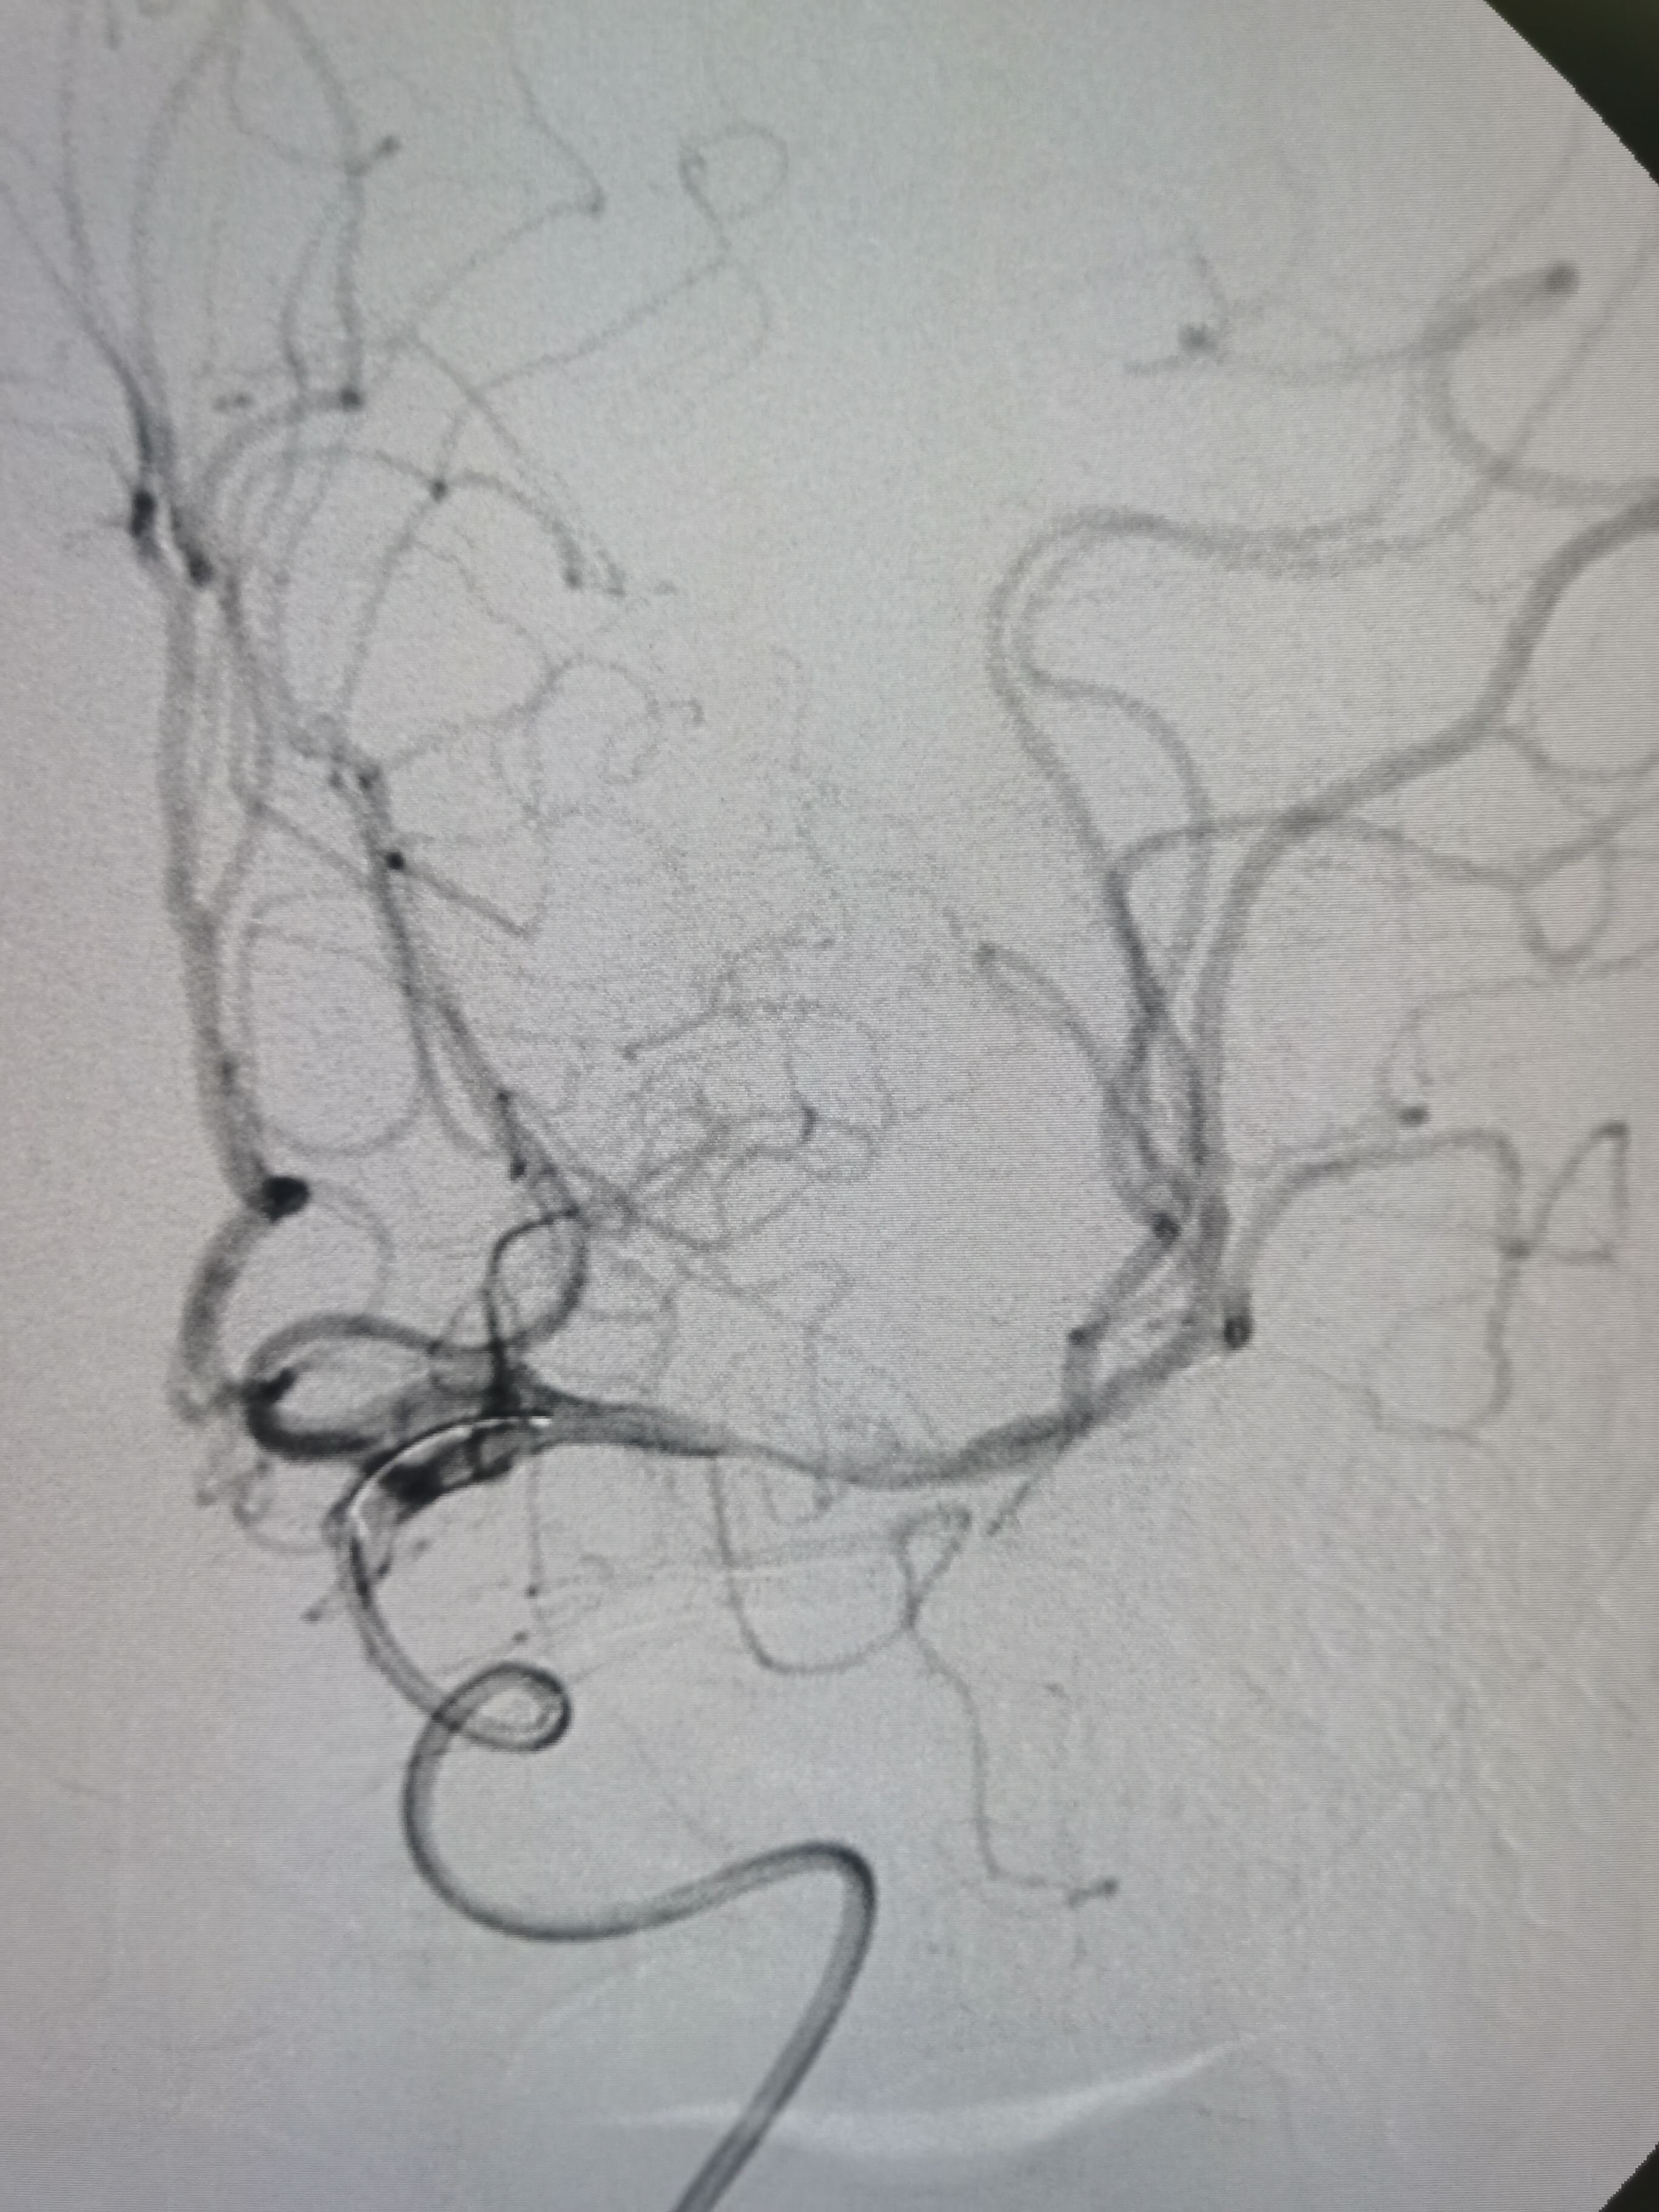

8F导引导管及中间导管迅速建立通路,微导丝携微导管顺利通过病变。

微导管确认位于真腔。

4/20取栓支架释放后血管再通。

SWIM技术取栓一次,取出的血栓。